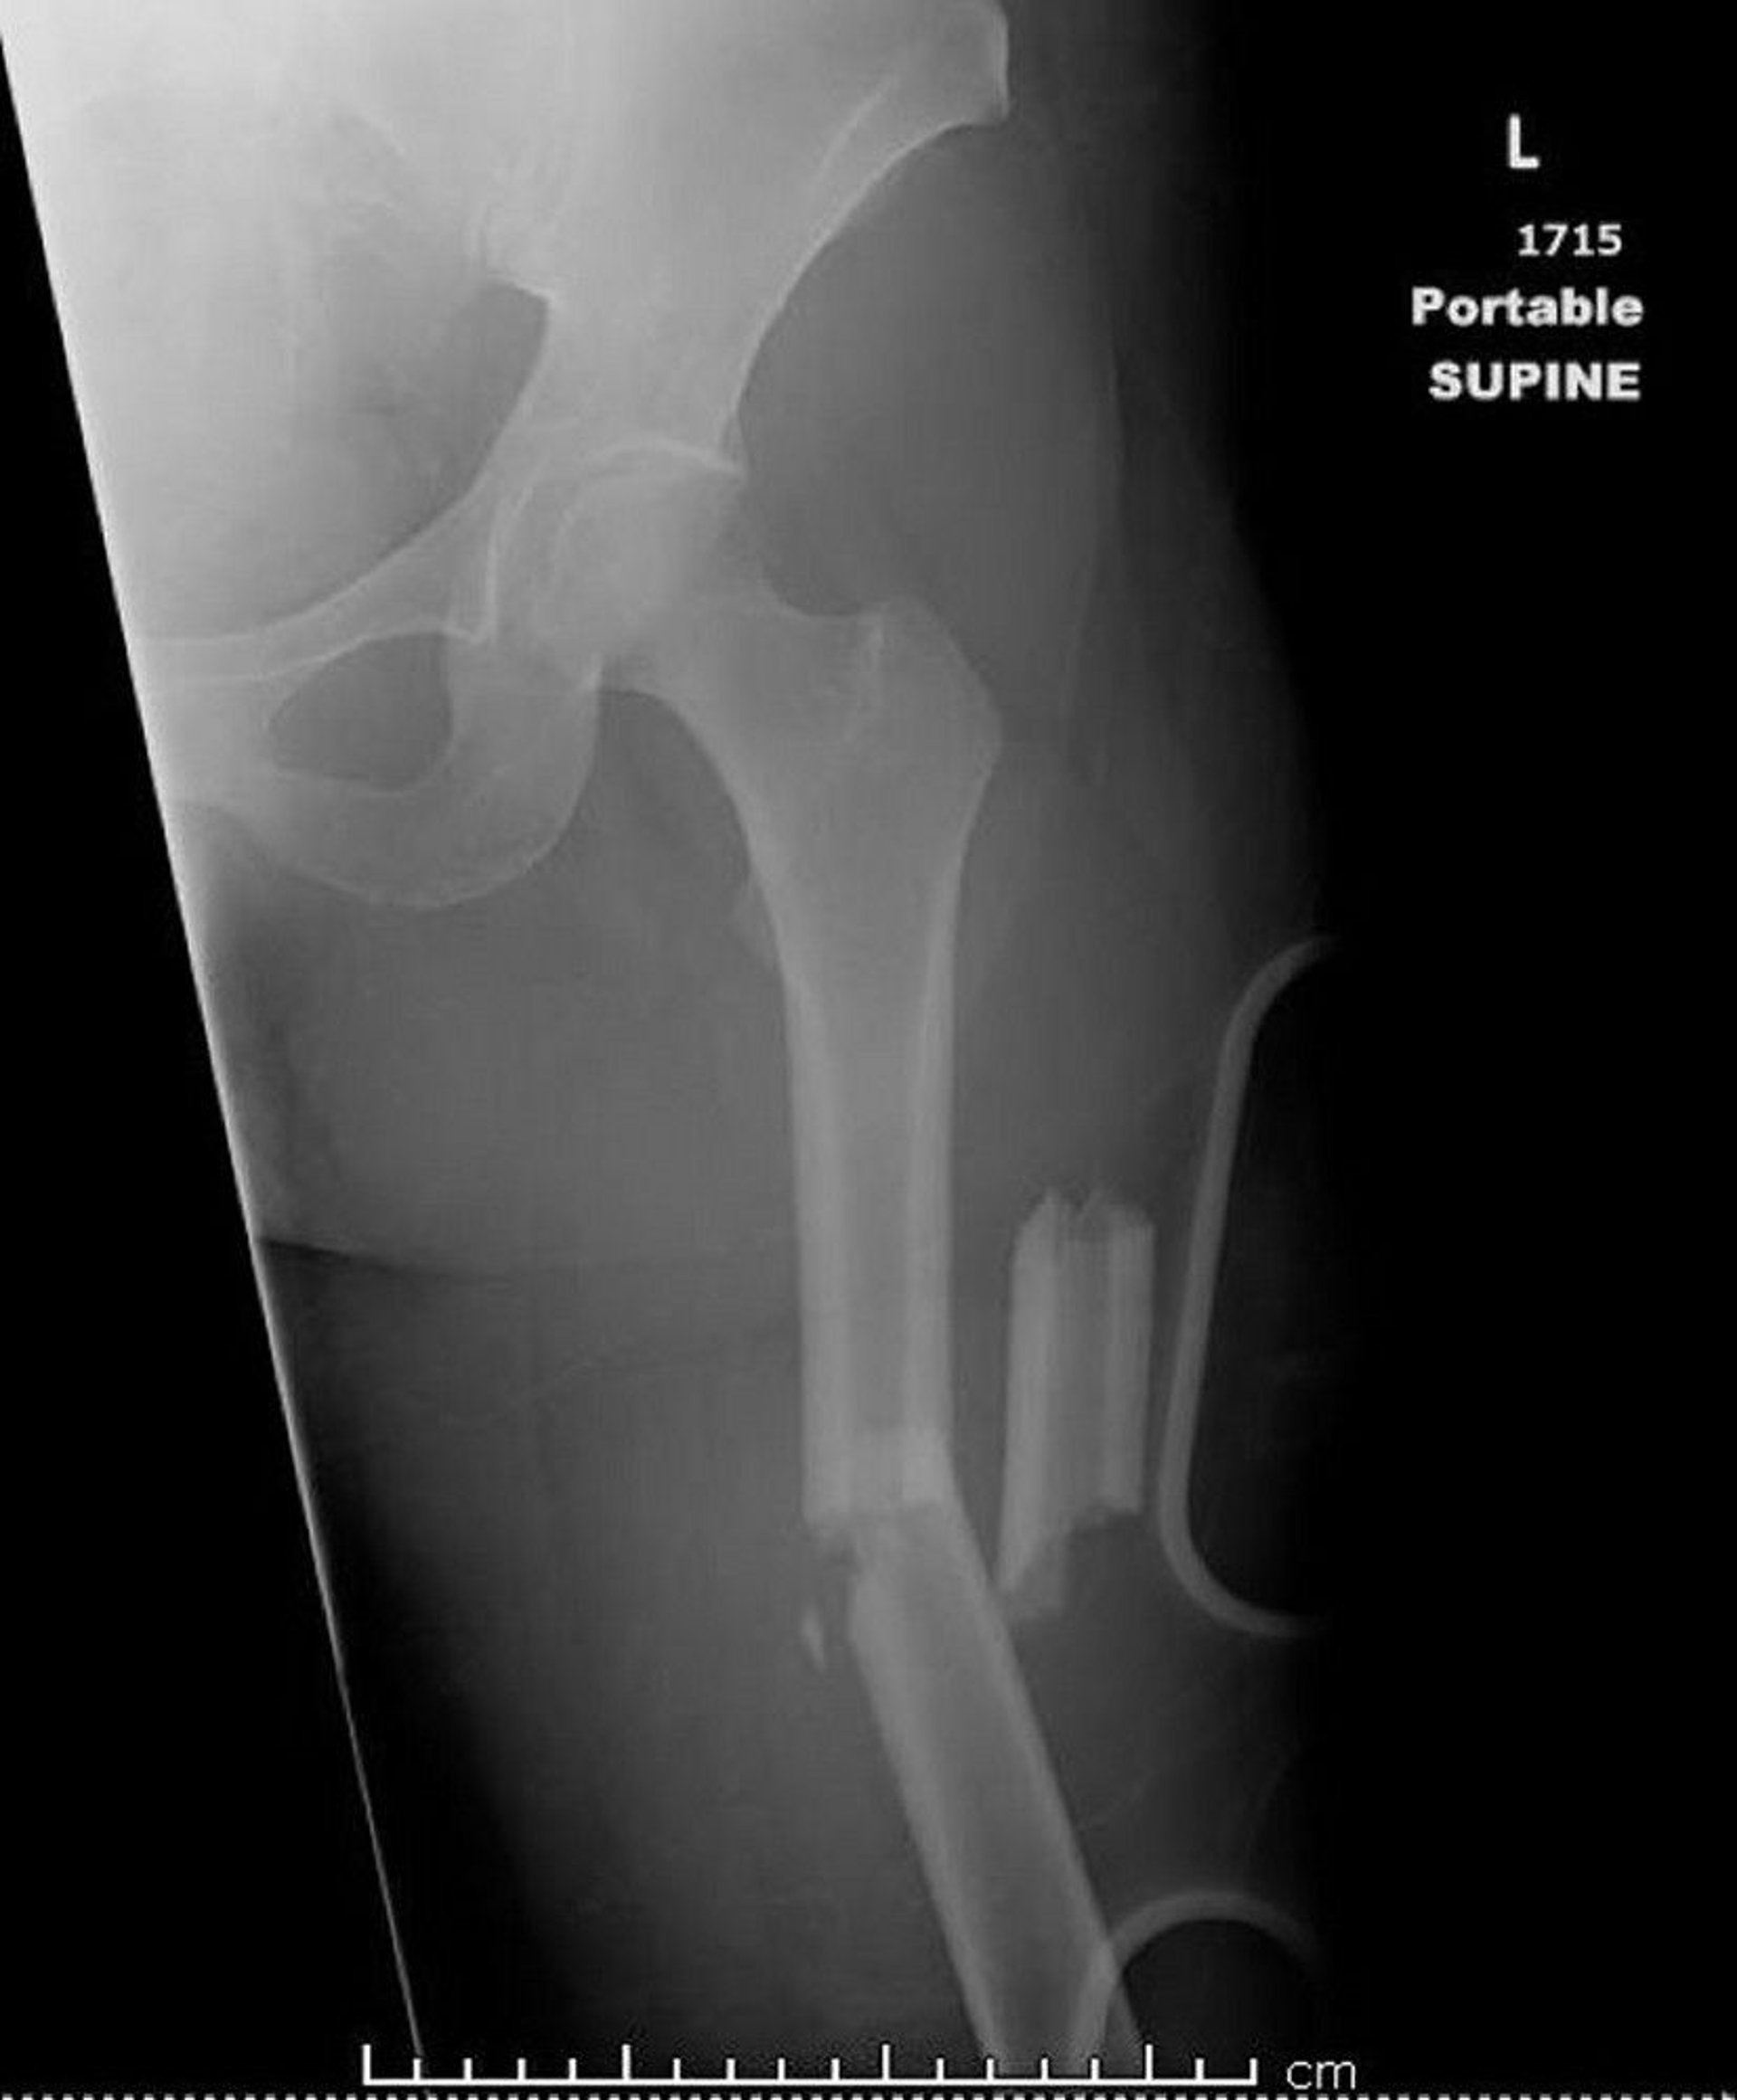

This image shows a femur that is fractured in more than two places (comminuted).

Image courtesy of Danielle Campagne, MD.